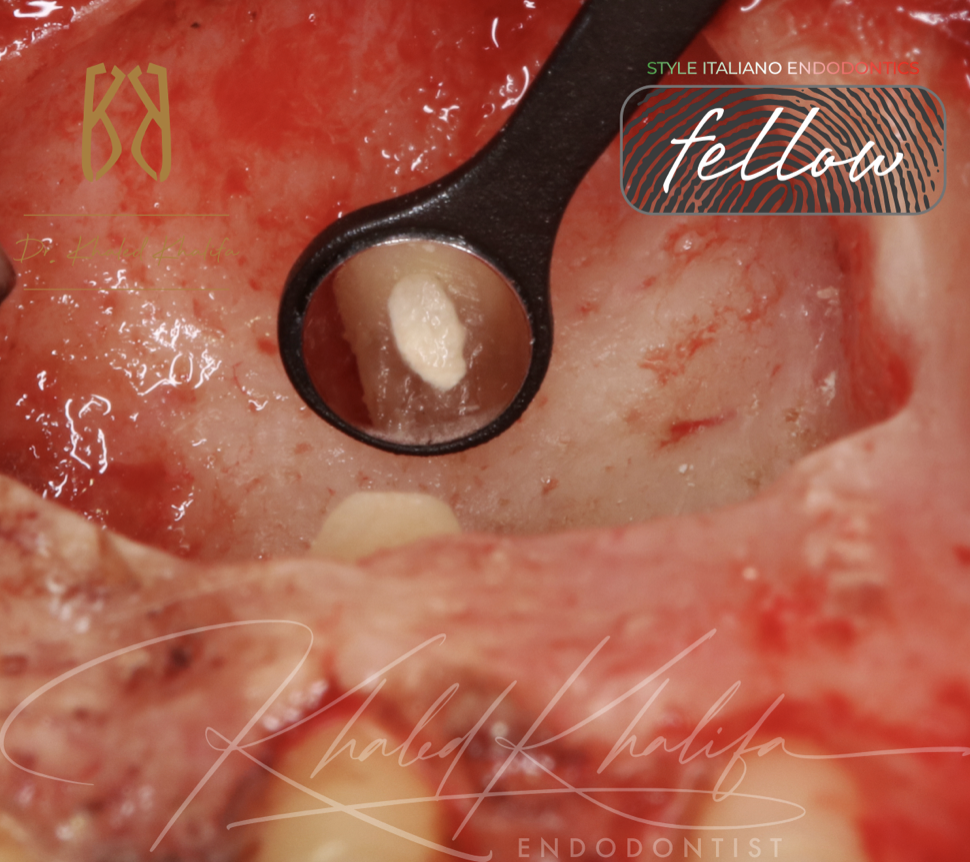

Endodontic Microsurgery is one of the most important ways to save teeth rather than extracting and placing implant.

Here we will talk about a tooth that failed multiple trials of endodontic treatment, endo-surgery was made and follow ups shows complete healing.